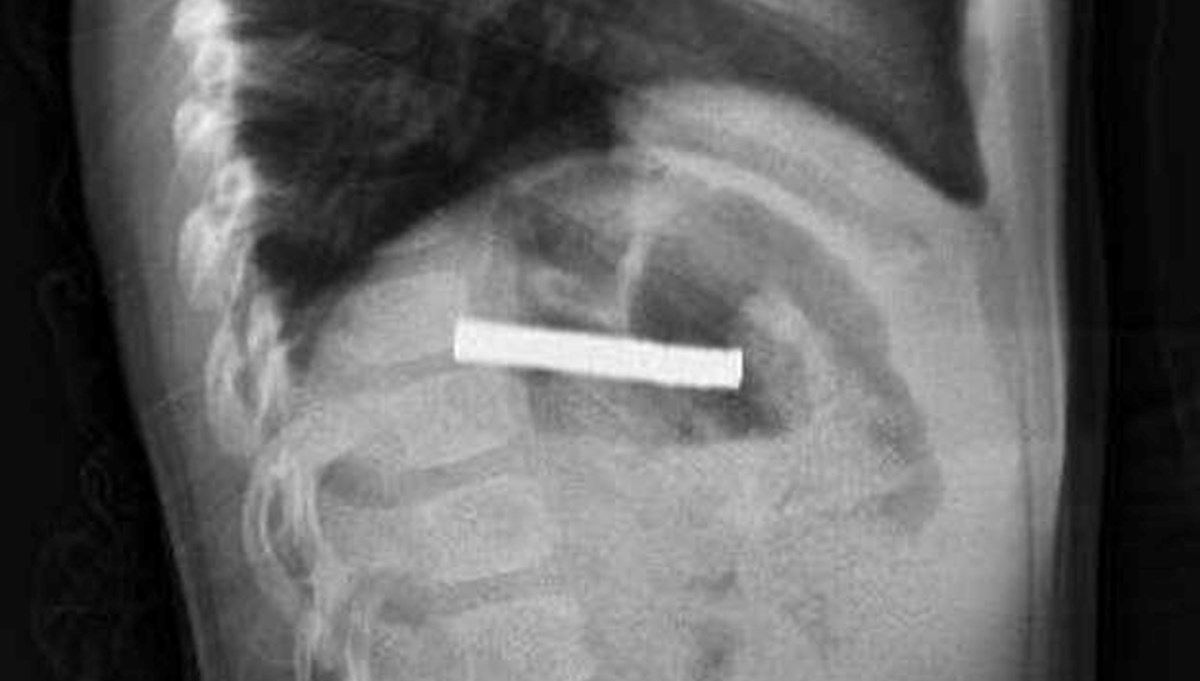

Elazığ’da 3 yaşındaki bir çocuğun yuttuğu 19 mıknatıs, Fırat Üniversitesi Hastanesi'nde başarılı bir operasyon ile çıkartıldı.

Fırat Üniversitesi Çocuk Gastroenteroloji Hepatoloji ve Beslenme Bilim Dalı Başkanı Prof. Dr. Yaşar Doğan, çocuk hastanın yemek borusuna yapışmış 19 mıknatısı endoskopik yöntemle çıkardı.

Mıknatıslar uzun süre yemek borusunda takılı kaldığı için yemek borusu ve mide girişinde zedelenmeler olurken, çocuğun sağlık durumunun iyi olduğu ve taburcu edildiği öğrenildi.